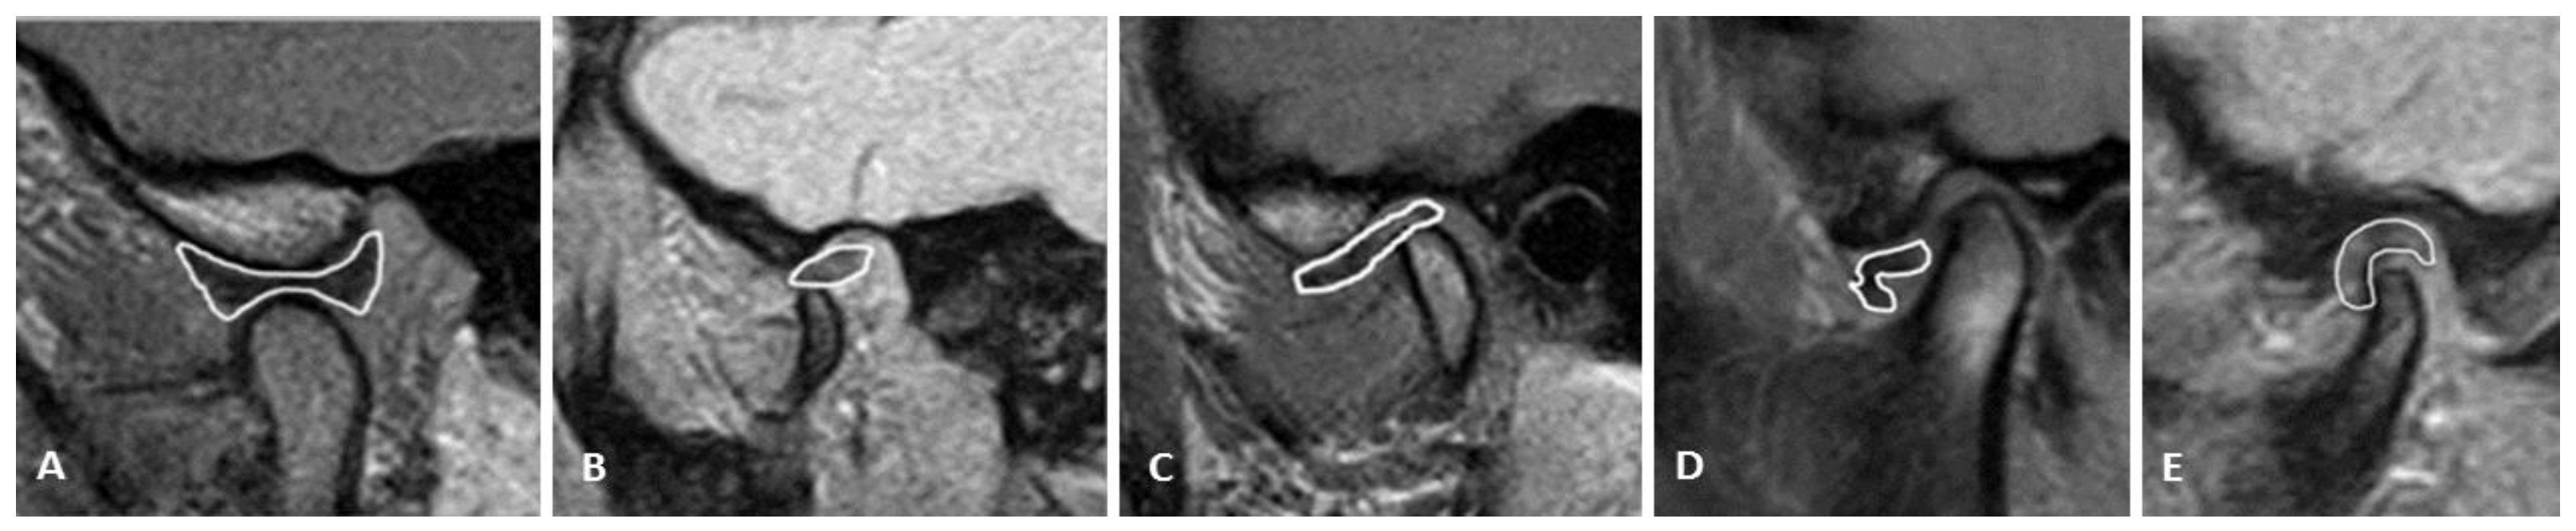

2.4. Analysis of TMJ